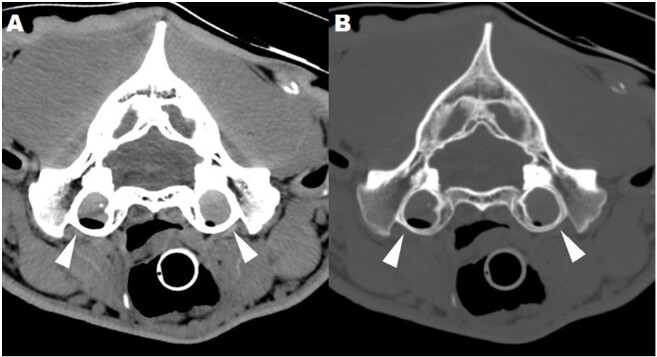

An 11-year-old male Bengal tiger (Panthera tigris tigris) was referred for a 2-week history of ambulatory tetraparesis, generalized ataxia, and hypermetric gait, associated with mild right head tilt and spontaneous proprioceptive deficit on the right forelimb. Neuroanatomical localization was C1-C5 myelopathy; cerebellum-vestibular system involvement was also considered. Hematology and serum biochemistry were unremarkable, although serum vitamin A (0.11 mg/L) was below the reference range (0.17 - 0.36 mg/L). Indirect hemagglutination test for Toxoplasma gondii was positive (antibodies titer 1:640). Computed tomography of the head and cervical column showed hypertrophic degenerative remodeling of the vertebral articular joint processes, causing severe vertebral canal stenosis and bilateral spinal cord compression at C2-C3. In addition, bilateral otitis media was present, without signs of intracranial extension of the inflammation by imaging. Brainstem auditory evoked potential test revealed a partial, bilateral conductive deafness. Cerebrospinal fluid (CSF) analysis resulted normal; CSF PCR for T. gondii was negative. A diagnosis of osseous-associated cervical spondylomyelopathy (OA-CSM) and concurrent bilateral otitis media was obtained. Glucocorticoids, movement restriction, vitamin A supplementation, and clindamycin were instituted. Four weeks later the clinical signs deteriorated, and the animal was euthanized. To the authors' knowledge this is the first report of OA-CSM in a tiger.